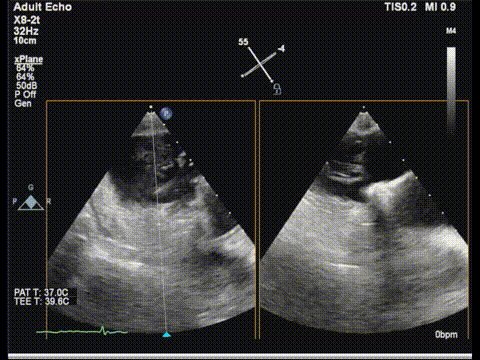

三尖瓣

三尖瓣反流以膈叶脱垂为主,反流主要集中在前叶和膈叶间,从中心区向边缘区的蔓延。后叶又有分了两个叶,分型上属于IIIb型的三尖瓣反流。

三尖瓣膈叶前叶

三尖瓣膈叶前叶color